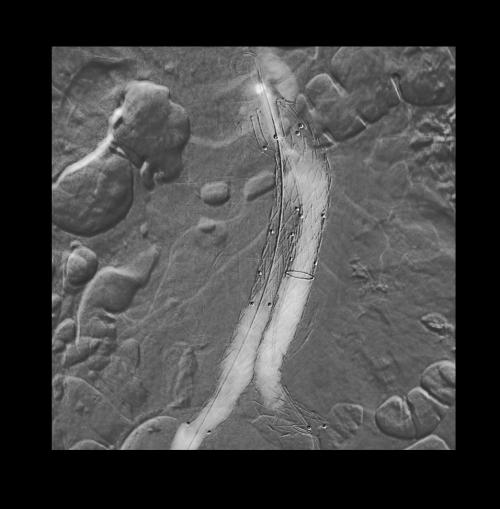

Zabieg EVAR z użyciem angiografii CO₂

Zespół chirurgów z Oddziału Chirurgii Naczyniowej i Endowaskularnej Śląskiego Centrum Chorób Serca w Zabrzu przeprowadził zabieg małoinwazyjnego leczenia tętniaka aorty brzusznej (EVAR) z wykorzystaniem angiografii z użyciem dwutlenku węgla (CO₂).

Zabieg EVAR z użyciem angiografii CO₂ - Zdjęcie główne

Zastosowanie tej metody umożliwia wykonanie procedury bez konieczności podawania klasycznego kontrastu jodowego, co ma szczególne znaczenie u pacjentów z upośledzoną funkcją nerek.

Angiografia CO₂ eliminuje ryzyko wystąpienia nefropatii pokontrastowej, dzięki czemu pozwala na bezpieczne leczenie chorych z dodatkowymi czynnikami ryzyka. To kolejny krok w kierunku stosowania nowoczesnych i bezpiecznych technik endowaskularnych, zwiększających dostępność skutecznego leczenia w Śląskim Centrum Chorób Serca w Zabrzu dla pacjentów wysokiego ryzyka.